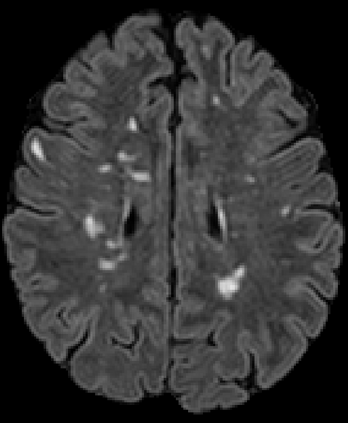

Recently, segmentation methods based on Convolutional Neural Networks (CNNs) showed promising performance in automatic Multiple Sclerosis (MS) lesions segmentation. These techniques have even outperformed human experts in controlled evaluation conditions such as Longitudinal MS Lesion Segmentation Challenge (ISBI Challenge). However state-of-the-art approaches trained to perform well on highly-controlled datasets fail to generalize on clinical data from unseen datasets. Instead of proposing another improvement of the segmentation accuracy, we propose a novel method robust to domain shift and performing well on unseen datasets, called DeepLesionBrain (DLB). This generalization property results from three main contributions. First, DLB is based on a large group of compact 3D CNNs. This spatially distributed strategy ensures a robust prediction despite the risk of generalization failure of some individual networks. Second, DLB includes a new image quality data augmentation to reduce dependency to training data specificity (e.g., acquisition protocol). Finally, to learn a more generalizable representation of MS lesions, we propose a hierarchical specialization learning (HSL). HSL is performed by pre-training a generic network over the whole brain, before using its weights as initialization to locally specialized networks. By this end, DLB learns both generic features extracted at global image level and specific features extracted at local image level. DLB generalization was validated in cross-dataset experiments on MSSEG'16, ISBI challenge, and in-house datasets. During experiments, DLB showed higher segmentation accuracy, better segmentation consistency and greater generalization performance compared to state-of-the-art methods. Therefore, DLB offers a robust framework well-suited for clinical practice.